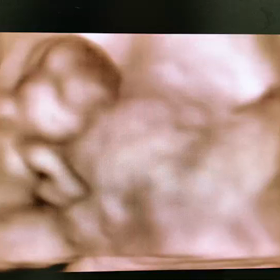

• 4D映像の画像

4D映像